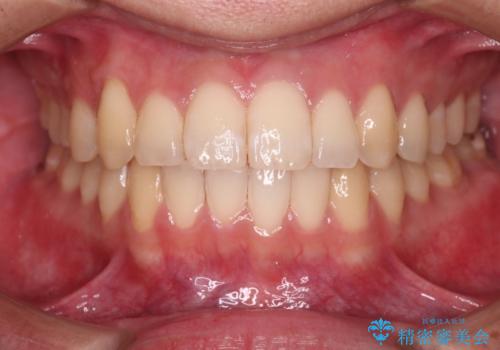

Dr. 菊地俊介の症例写真

【インビザラインとワイヤー矯正】がたつきと噛み合わせを改善!